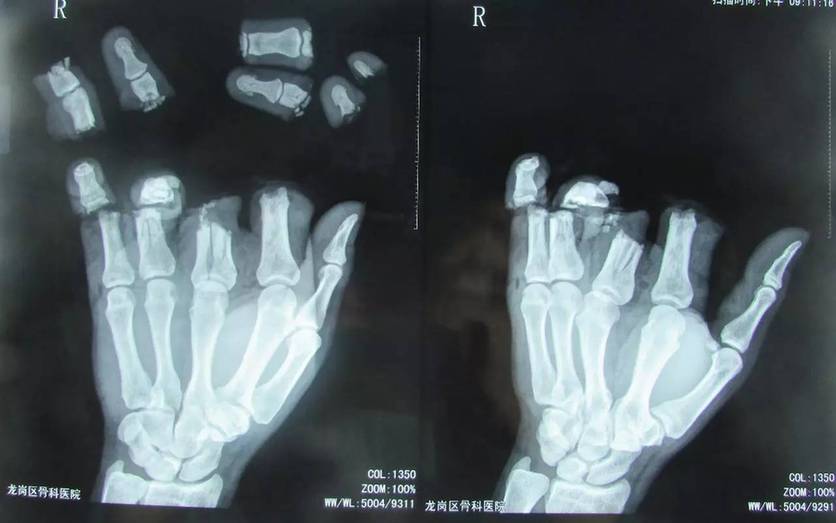

新闻提要 事发4月12日下午,深圳光明新区一家工厂内,一名四十多岁的男性工人不慎被机器压伤右手,除大拇指外,4根手指碎成8段。

事发4月12日下午,深圳光明新区一家工厂内,一名四十多岁的男性工人不慎被机器压伤右手,除大拇指外,4根手指碎成8段。